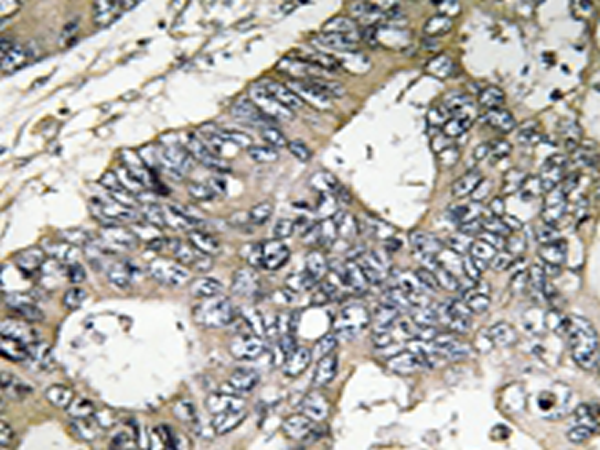

IHC positive control:

Human colon carcinoma tissue

IHC Recommend dilution:

50-100